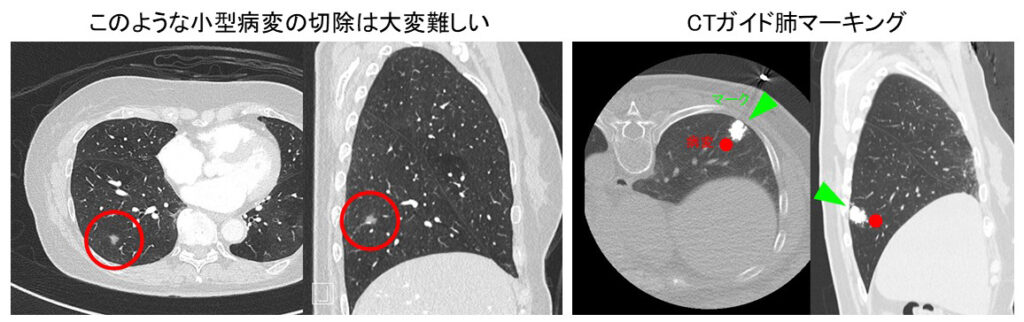

小型肺病変のマーキング技術

- 健診で見つかる小型肺病変(図左上)をどうしたらよいかというご相談はもっとも多いご相談のひとつである。肺の表面はツルツルで、なにもせずに手術室で病変がどこにあるかを定めることは難しく、肺のマーキング技術が必要となる。マーキング技術がないと、小型の病変を切除するために、かえって無駄に大きく肺を切除してしまったり、切除し損ねたりする恐れがあり、小型病変の切除では安全で明瞭な病変位置のマーキング技術が必須である。

- 当科では蛍光色素によるCTガイド肺マーキング法(ICGオーバーレイ法)を考案し多く実施してきた(図右上)。本法は合併症がほぼなく安全に実施でき、明瞭な発光として病変位置を同定でき(図中)、病変位置が大変わかりやすい。この技術によって胸腔鏡やロボットによる正確な肺部分切除・肺区域切除を行うことができる。当科の得意とするところである。

- このマーキングと肺血管気管支構造(図下)とを組み合わせることで、切除範囲を立体的にイメージし精緻な手術を行っている。